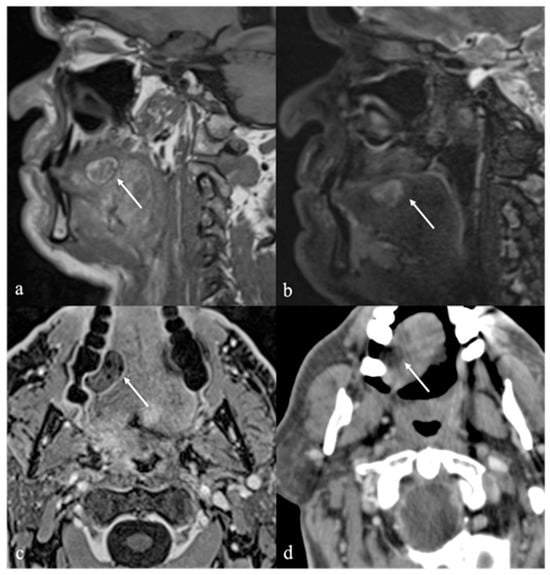

6. Dermoid Cysts

7. Thyroglossal Duct Remnants

7.1. Thyroglossal Duct Cyst

| Dermoid cyst [1,13,14] | CT: free fat and calcified corpuscles (“sack of marbles” sign) | Vascular malformation, epidermoid cysts, lipoma |

| Epidermoid cyst [14] | MRI: high SI on DWI, and restricted diffusion with low values on ADC map | Vascular malformation, dermoid cysts |

| Thyroglossal duct cyst [15] Ectopic thyroid tissue [16] | Cyst Same features as thyroid tissue | Lingual tonsil mucous retention cyst Squamous cell carcinoma and lymphoma of the tongue base |